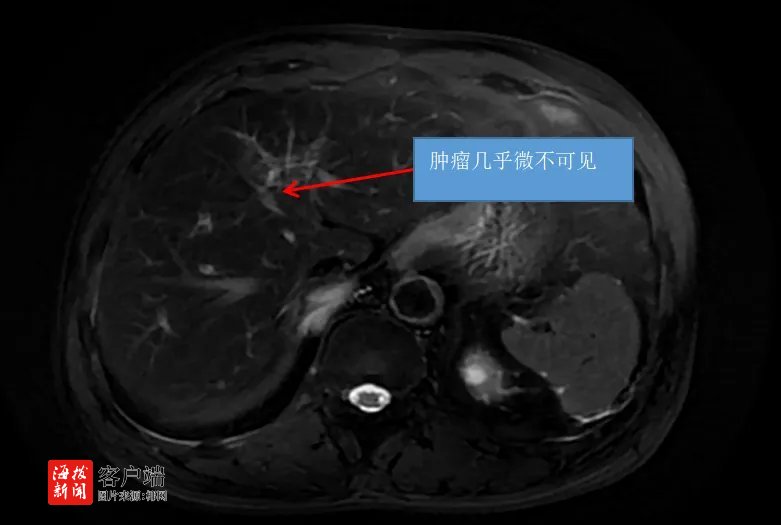

2023年7月,该院肝胆胰外科团队为王老伯实施了第一次灌注化疗。手术后,王老伯恢复较好,肝胆胰外科团队于灌注化疗术后第二天给予王老伯行肿瘤免疫治疗,整个疗程约一周。在该院肝胆胰外科,王老伯共进行了两次肝动脉灌注化疗(HAIC)联合靶向+免疫规范化治疗及一次D-TACE治疗。

今年3月,王老伯在海医一附院复查了肝脏增强MRI,结果表明,经过系统规范的治疗后,王老伯肿瘤较前明显缩小,几乎微不可见。